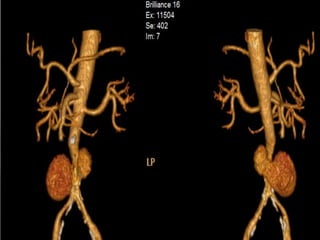

Occlusion of left subclavian artery, severe narrowing

of distal thoracic aorta and left common carotid art.

TAKAYASU ARTERITIS (type2).